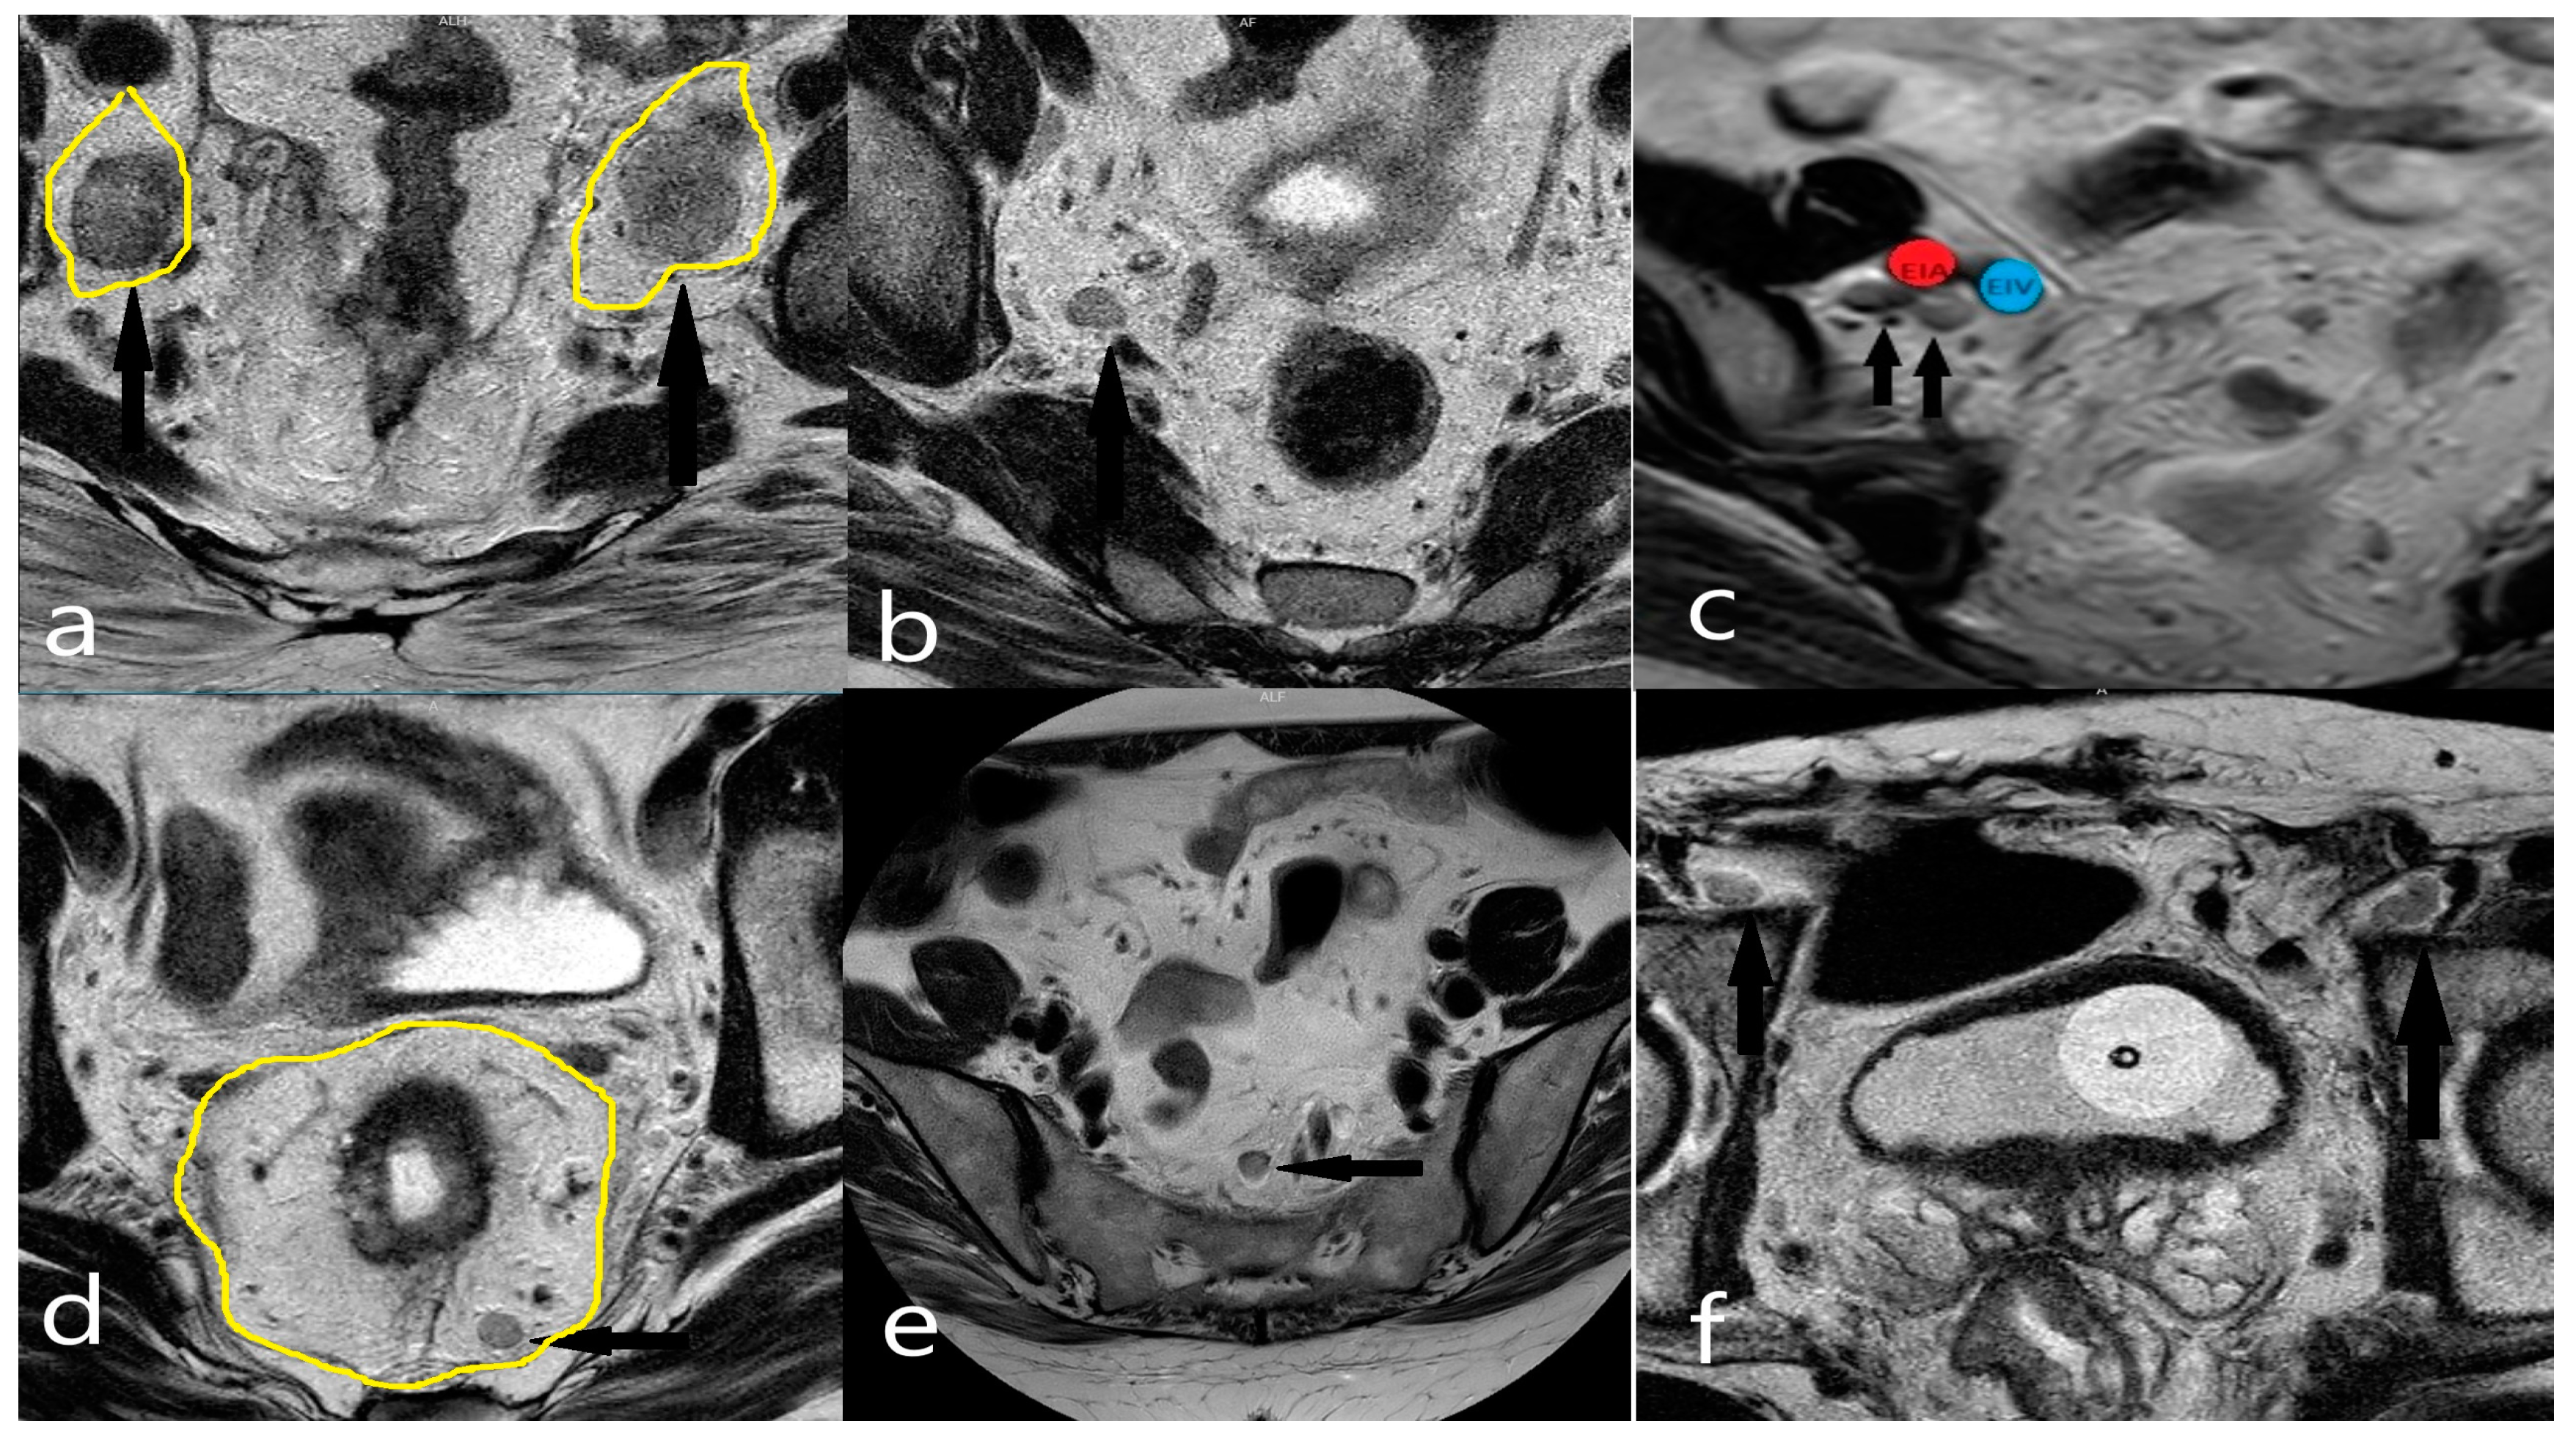

2.4. MRI Evaluation

2.5. Anatomical Classification of Lateral Lymph Nodes and Classification of Pathological Lymph Nodes Based on Size